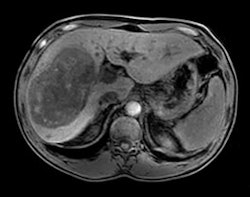

An mDixon scan using Philips' Ingenia MRI system with dStream. Image courtesy of Philips.

MRI

Upgrades and enhancements are being highlighted in the MRI section of Philips' booth, such as SmartPath to dStream, the company's digital broadband MRI technology. The firm is touting the latest release of dStream, which includes applications in neurology, trauma, pediatrics, and fatty liver patients, as well as routine fat saturation.